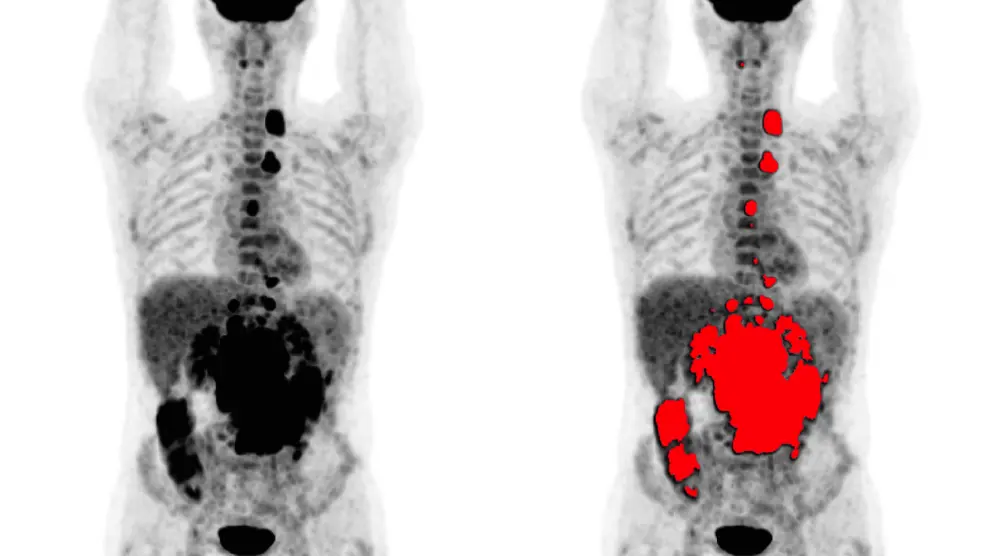

Además, según informan, este nuevo desarrollo permite aumentar de manera significativa su extensión axial y abarcar el cuerpo completo del paciente. Además, la tecnología podrá reducir más aún la dosis de radiación asociada a este equipo, lo que tendrá un efecto beneficioso directo en los casos de seguimiento de respuesta a tratamientos en los que son necesarios realizar varios estudios PET.

Los dispositivos PET se centran en la obtención de imágenes moleculares, que utilizan radiofármacos específicos para generar la imagen funcional de un órgano o proceso metabólico en particular. La imagen molecular mediante PET está ayudando en todas las etapas del estudio oncológico del paciente, tanto en el diagnóstico inicial como en el seguimiento, guía para biopsia o planificación de quimio/radioterapia.